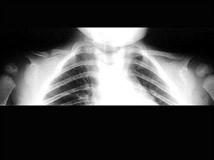

男,2岁,发育迟缓,头颅软,结合图像,最可能的诊断是?(?)A.成骨不全B.颅锁骨发育不全C.马方综合征D.软骨发育不全E.黏多糖病

问题 男,2岁,发育迟缓,头颅软,结合图像,最可能的诊断是?(?)

选项 A.成骨不全 B.颅锁骨发育不全 C.马方综合征 D.软骨发育不全 E.黏多糖病

答案 B